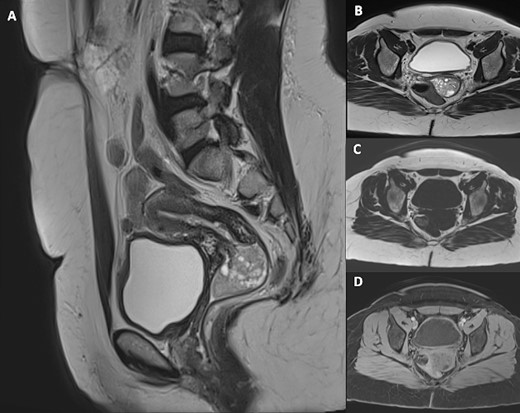

Pelvic magnetic resonance imaging (MRI) revealed a 5 cm × 3 cm × 3 cm intravaginal mass, with endocervical implantation, well-defined, featuring slightly lobulated margins and an oval shape. The mass exhibited the same signal as the endometrium: isointense on T1-weighted images, moderate hypersignal T2 intensity, containing areas of marked hyperintensity on T2. There was no diffusion restriction, and a slight enhancement was observed after Gadolinium injection (Figs 2 and 3). This finding primarily suggested a cervical polyp delivered through the uterine cervix.

Pelvic MRI including sagittal T2-weighted (A), axial T2-weighted (B), axial T1-weighted (C) and axial post-Gadolinium injection (D) images, demonstrating a 5 cm × 3 cm × 3 cm intravaginal mass with endocervical implantation. The mass is well defined, featuring a slightly lobulated oval shape. It exhibits the same signal as the endometrium: isointense on T1-weighted images, moderate hypersignal T2 intensity, containing areas of marked hyperintensity on T2 with slight enhancement after Gadolinium injection.